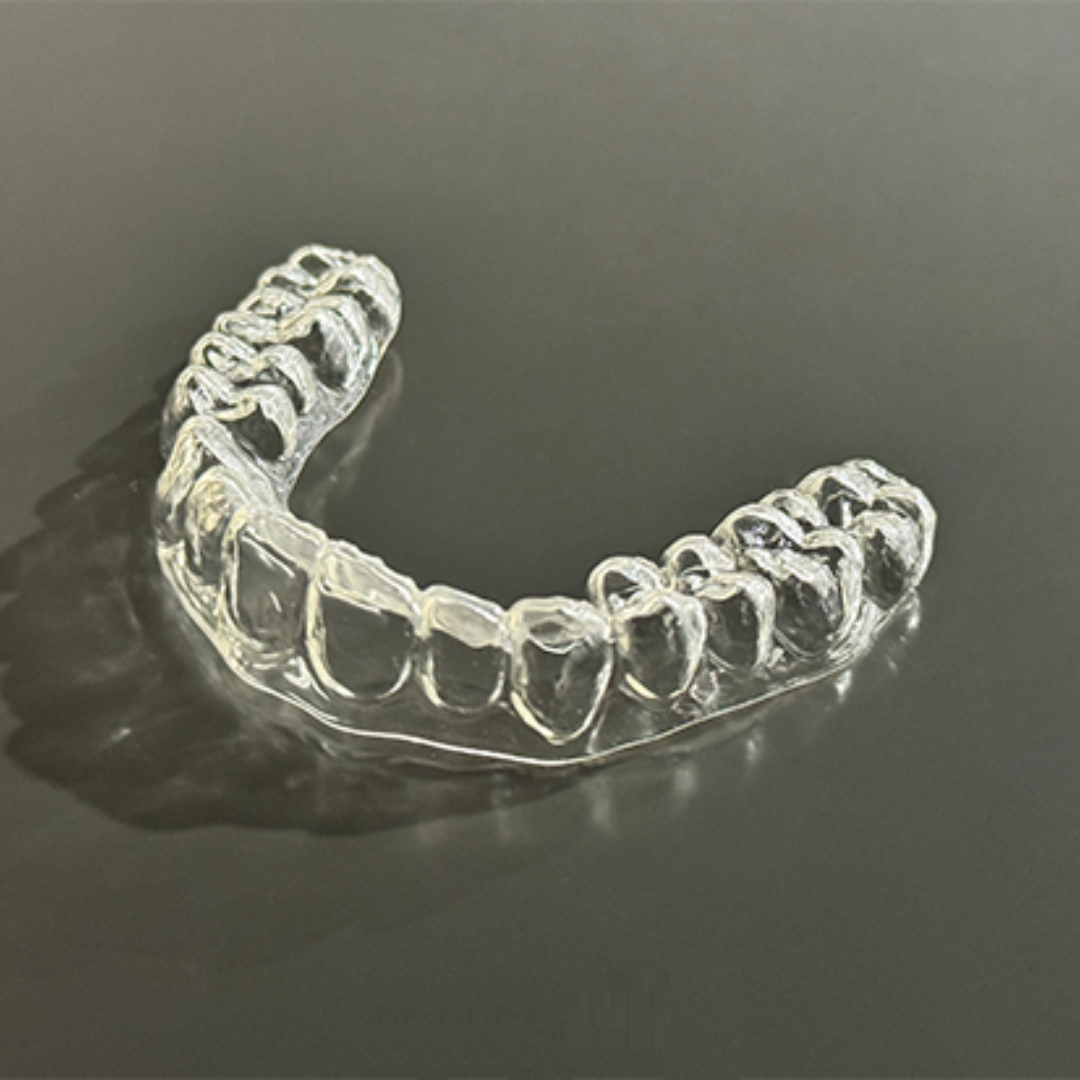

앞니 사이 벌어진 공간과 정중선 불일치를 고민으로 내원하셨던 20대 남성 환자분입니다. 윗니, 아랫니 공간이 각각 3.4mm, 2.6mm 가량 벌어져있고, 위와 아래의 중앙선 차이가 2.1mm 정도로, 상대적으로 정중이개와 정중선 불일치가 눈에 띄는 모습입니다. 해당 환자분께서는 격투기를 취미로 하시는 분이셔서 교정장치를 부착한 채로 얼굴 부위에 타격이 있을 경우 입 안이 다칠까봐 걱정이 있으셨습니다. 교정 진단 상담 후 고민 끝에 부상 방지를 위해 표면이 매끈한 투명교정 장치로 치료하시기로 결정하셨습니다.

최근에는 티 나지 않는 교정을 원하시는 심미적인 이유 뿐만 아니라, 위생 관리, 음식물 섭취, 부상 방지 등 다양한 이유로 전통적인 부착식 교정장치 대신 투명 교정을 선택하시는 환자분들이 부쩍 많아지셨습니다. 투명 교정 치료는 결과는 동일하면서 사진 촬영, 운동, 여행 등 일상 생활에 제약이 크게 없다는 점이 큰 장점입니다. 다만, 증례에 따라 부착식 교정장치가 더 빠르고 효과적인 경우도 있어 교정 치료 전 전문의와의 상담을 통해 결정하는 것이 좋습니다. ^^ 총 32주 간의 교정 치료가 종료된 모습입니다. 기존에 가장 고민이셨던 공간 벌어짐, 정중선 불일치가 예쁘게 수정되었습니다. 2025.5.18.